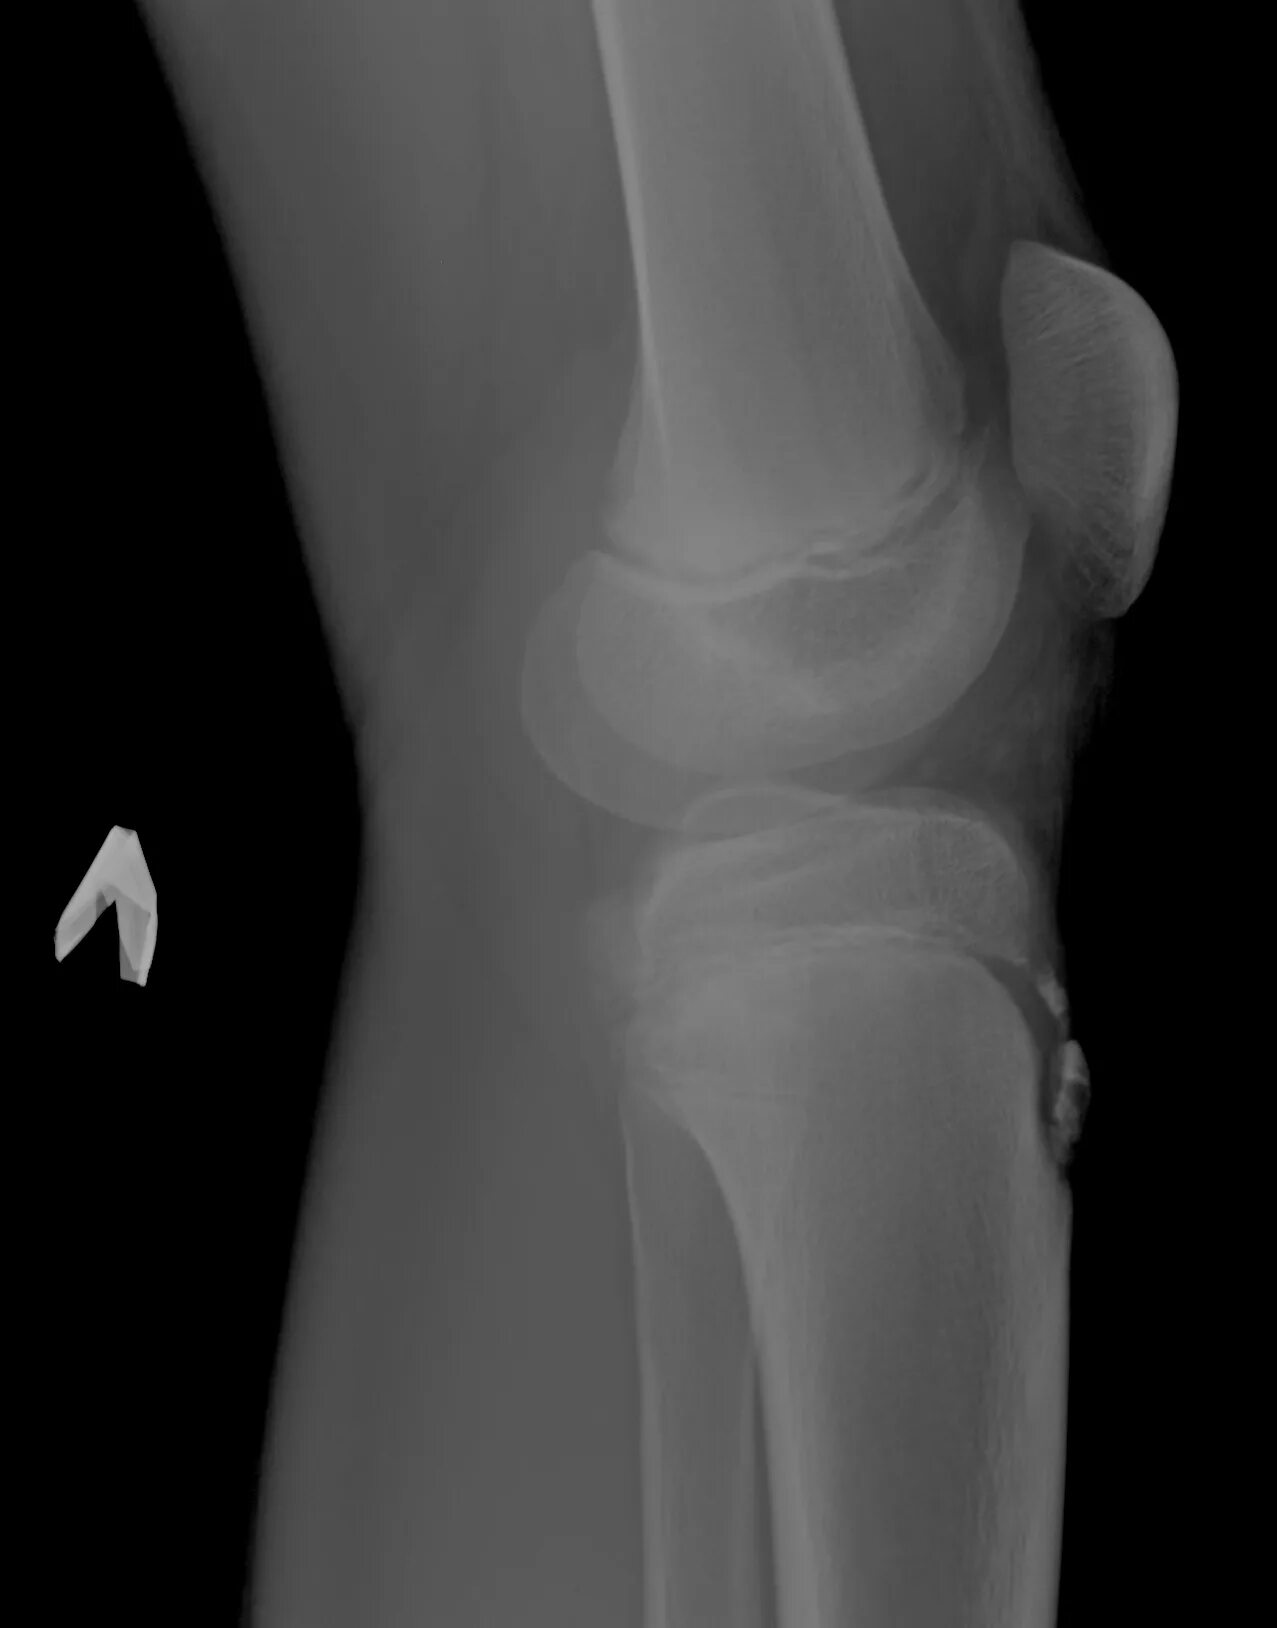

Код мкб шляттера